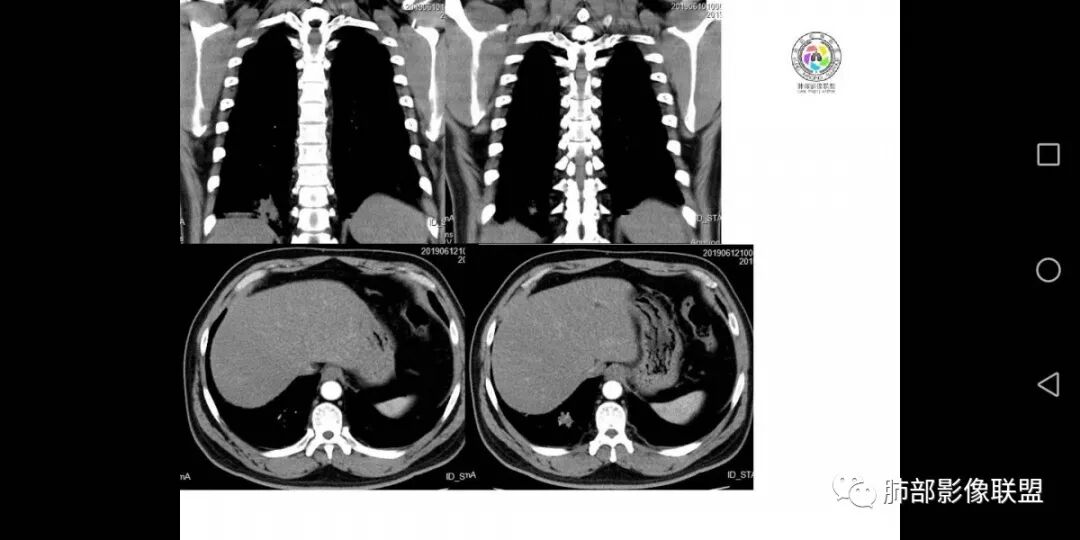

患者男,45岁,因乏力、低热、心悸入院,最高体温38℃,偶有咳嗽、无咳痰、咯血,肿瘤标志物阴性。

影像资料

中年男性,乏力  低热入院,胸CT:右肺下叶后基底段结节样病变,病灶周围可见细支气管扩张,病灶边缘可见短软毛刺,病灶周围有毛玻璃影,冠状位肺窗病灶与膈胸膜呈宽基地,纵隔窗可见病灶内空洞及低密度区,增强明显强化及延迟强化,考虑良性感染性病变,隐球菌肺炎?,结核?。但在冠状位肺窗有一支细支气管在病灶旁有截断,还得除外肺癌的可能性。

患者中年男性,以乏力、低热、心悸入院。胸部CT:右肺下叶后基底段近胸膜实性结节灶,病灶周围磨玻璃模糊影,可见短毛刺,边缘呈刀切、平直,冠状位肺窗病灶与膈胸膜呈宽基地,纵隔窗可见病灶内空洞及低密度区,增强明显强化及延迟强化,综合考虑良性感染性病变。肺隐球菌病可能大,机化性肺炎、腺癌次之,结核待排。

影像特点:多灶实变(多为双侧非对称性分布,部分病灶有一定的游走性)、单发或多发结节、反晕征。

分布特点:胸膜下和沿支气管血管束分布、条带状实变、小叶旁实变。

1.多位于肺表浅部位,近胸膜或叶间裂。